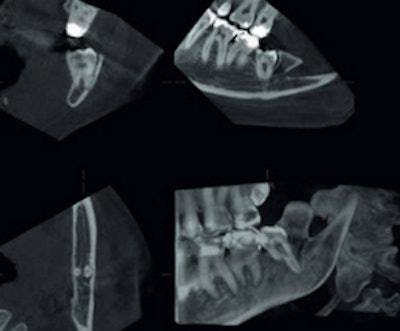

An example of cone-beam CT. In this instance, the lower left third molar (d. 38) was imaged after panoramic radiograph with CBCT. The arrows mark the mandibular canal. Images courtesy of Dr. Anni Suomalainen.

CBCT is a radiographic imaging method that allows accurate 3D imaging of hard tissues. During a CBCT scan, the scanner rotates around the patient's head (180° to 360°), obtaining multiple sequential planar projection images by a 2D detector. The scanning software collects the data, which are then processed to create a volumetric dataset with isotopic voxels with varying field-of-view.